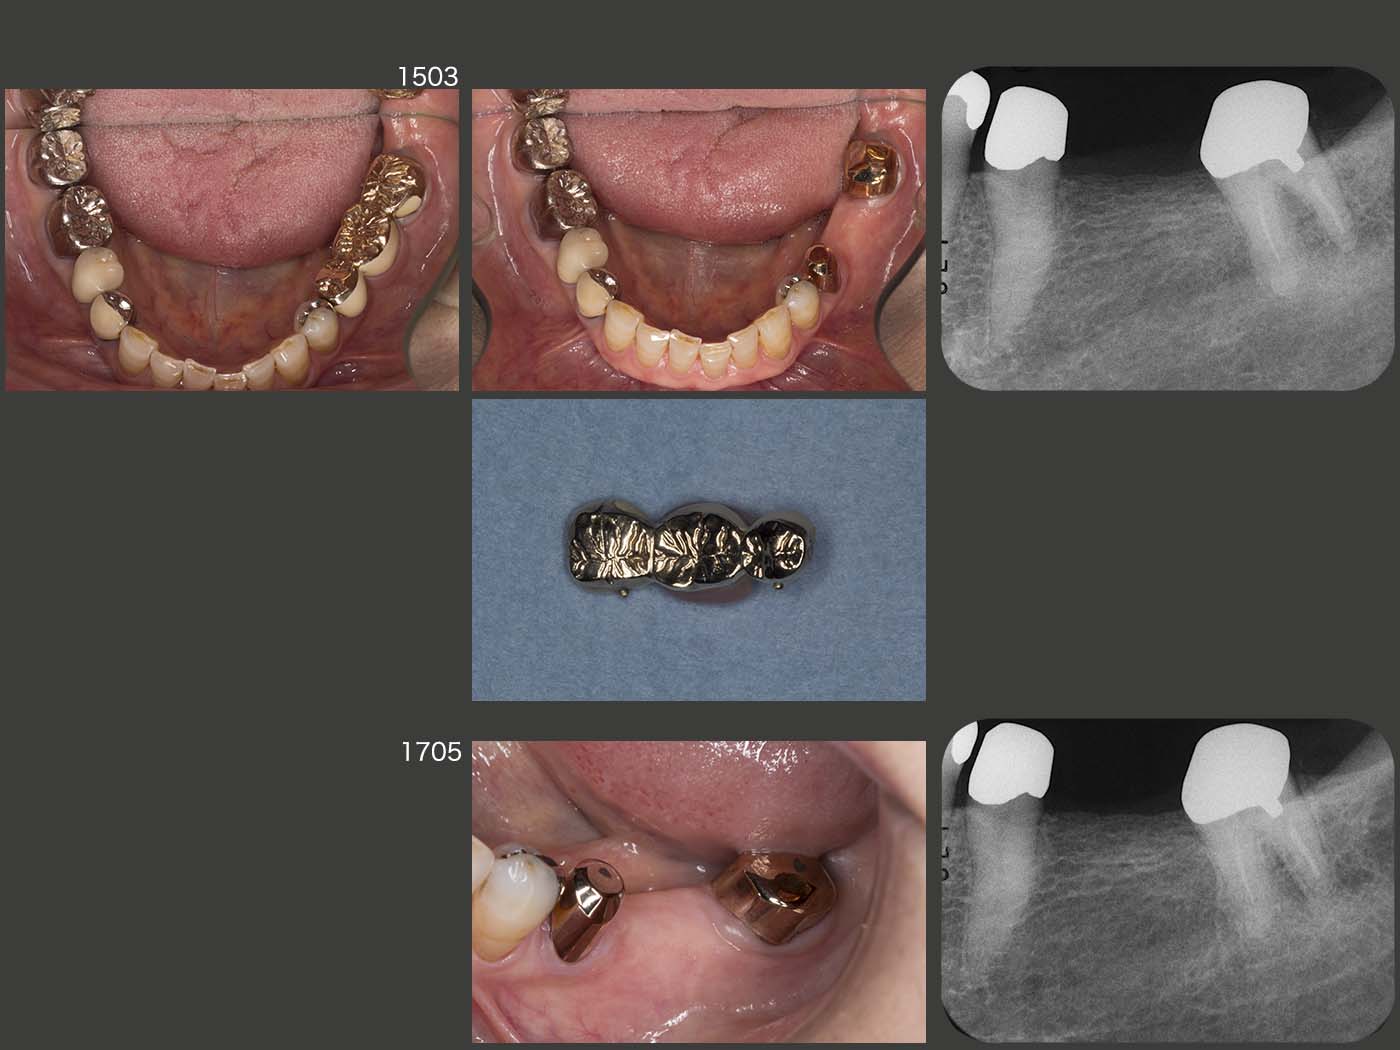

1999年初診、55歳女性。スライド上段3枚は、2012年11月の状態。2014年6月、夜間就寝時に左下7に痛みが出たとのことで来院した。デンタルX線写真に以前から根尖病変がみられたが、咬みしめの可能性も否定できず、暫く様子をみてもらった。しかし、7月に激痛が生じ、これは根尖病巣による急性症状と診断した。抗生剤を投与したのち感染根管治療を数回行ったが、根管が閉鎖しており内科的な治療は不可能と診断した。そこで8月、まず3週間にわたり、左下7の矯正的挺出を行い、抜歯しやすいように細工した。9月、歯の動揺を確認したのちに抜歯を行い、口腔外でスーパーボンドにより根尖を封鎖した。直ちに元の場所に戻し、隣在歯と3週間固定した。3ヵ月経過を観察し、補綴処置に移行した。